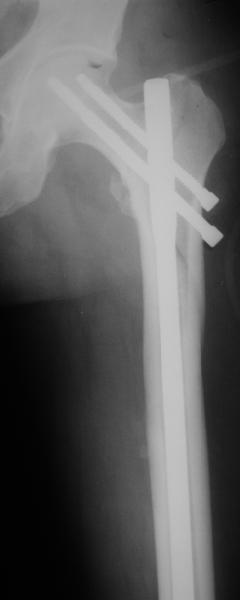

Как раз недавно у меня был примерный случай: больному 36 лет, поступил ночью, травма в результате мотоциклетной аварии, кроме чрезвертельного и спирального перелома левого бедра имеется переломы костей предплечья с этой же стороны. Скелетное вытяжение, а на следующий день больной про оперирован на ортопедическом столе с дистракцией. Чтобы не расколоть чрезвертельный перелом провели временную спицу ближе к переднему кортексу, из малого разреза костодержатель для репозиции, а фиксацию провели антиградным штифтом. Этапы операции на снимках.

Джолдас Кульджанов

Да, сейчас это и у нас самый напрашивающийся выбор. Сделали гвоздем ChM, картинки в приложении.